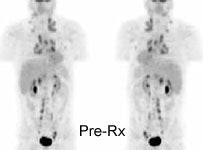

Monitor response to therapy in lymphoma: The patient shown below was a 29 year old male with a history of recurrent lymphoma despite chemotherapy and stem cell transplant. The patients initial PET scan (left) demonstrated extensive nodal disease throughtout the neck, chest, abdomen, and pelvis. The patient was treated with a repeat stem cell transplant. A post-treatment FDG PET exam demonstrated interval resolution of previously identified sites of disease consistent with a response to therapy. Note renal collecting system activity on both studies. The exams were performed on a Siemens ECAT EXACT PET scanner (manufactured by CTI). Case courtesy of North Texas Clinical PET Institute, Dallas, Texas and CTI PET Systems, Inc. Click images to view cine avi file (230K) |

|

Monitor response to therapy in lymphoma: The patient shown below is a teenage male with Hodgkins disease. The pre-therapy scan confirmed disease only above the diaphragm. The post-therapy scan was performed following two cycles of chemotherapy and demonstrated complete resolution of all sites of disease. Early data indicates that following effective chemotherapy, there is a rapid decrease in metabolic activity within the tumor. Click images to view rotating avi files (note para-cardiac and costophrenic angle nodes can also be seen on these images). |